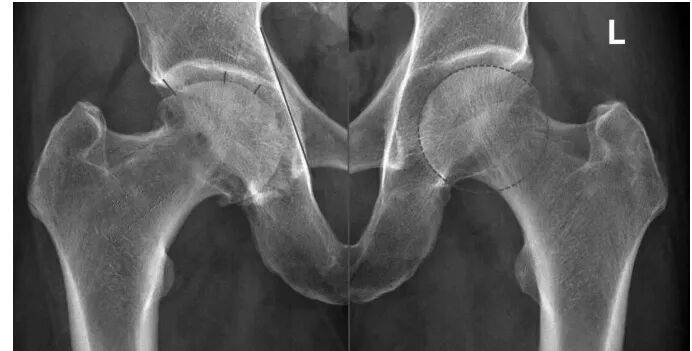

股骨头坏死发展到一定阶段,会出现“裂缝”(软骨下骨折)、“空洞”(囊性变)等。其实,股骨头内有“空洞”,不一定意味着坏死。下面,我举例说明。 病例 这是一位男性患者,今年67岁,6个月前无明显诱因出现